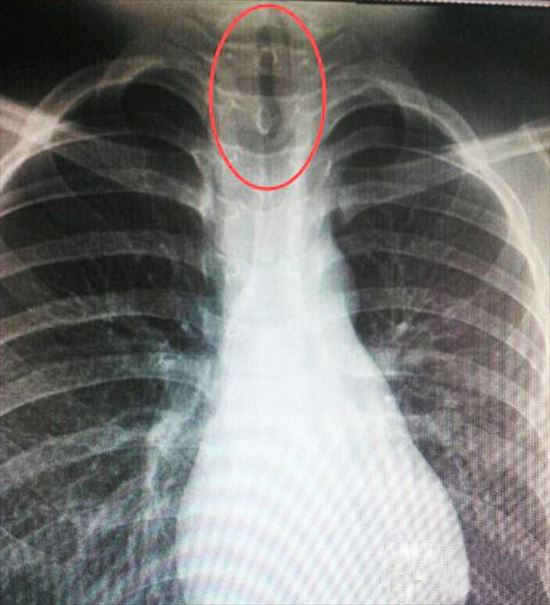

ในที่สุดแม่จังตัดสินใจพาลูกชายไปพบแพทย์ และสิ่งที่แพทย์พบจากการเอกซเรย์ก็สร้างความตกตะลึงไปตาม ๆ กัน เมื่อต้นเหตุอาการเจ็บในคอของเด็กชายมาจากปลิงขนาดตัวยาว 7 เซนติเมตรที่ดูดติดอยู่ที่ผนังหลอดลม และเมื่อมันขดตัวก็ยังขวางทางเดินหายใจ ทำให้ได้รับออกซิเจนไม่เพียงพอ เป็นเหตุทำให้เด็กชายเป็นลมอยู่บ่อย ๆ